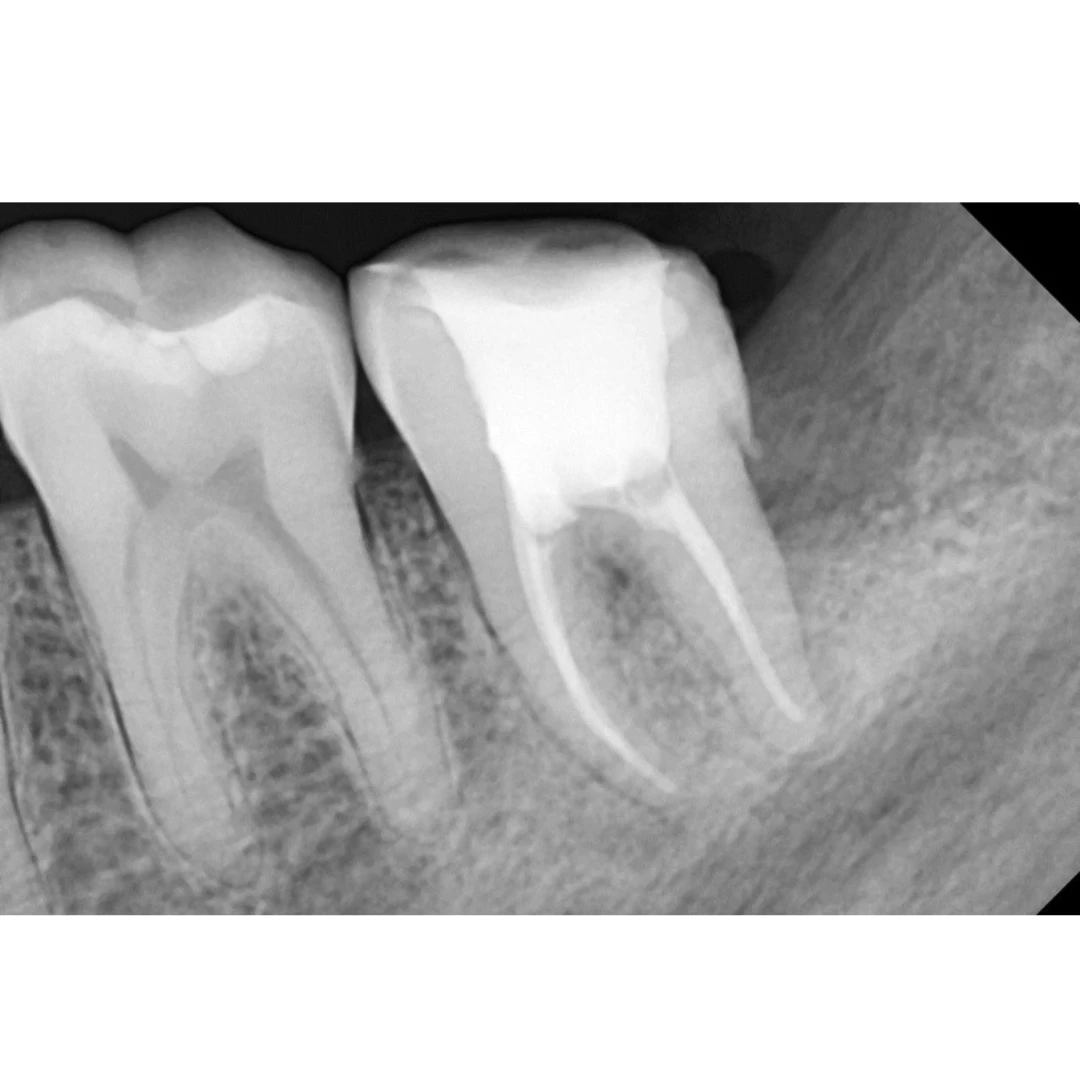

Impacted Wisdom Tooth Causing Food Impaction Leading to RCT of Adjacent Molar